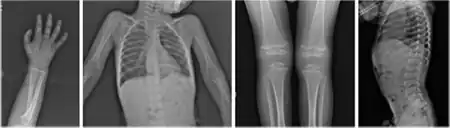

| Radiograph of a WRS child presenting with dysplastic bone growth in various regions of the body. | |

Wolcott–Rallison syndrome, WRS, is a rare, autosomal recessive disorder with infancy-onset diabetes mellitus, multiple epiphyseal dysplasia, osteopenia, mental retardation or developmental delay, and hepatic and renal dysfunction as main clinical findings. Patients with WRS have mutations in the EIF2AK3 gene, which encodes the eukaryotic translation initiation factor 2-alpha kinase 3.[1] [2] Other disease names include multiple epiphyseal dysplasia and early-onset diabetes mellitus.[3] Most patients with this disease do not survive to adulthood .[4] The majority of WRS patients die from fulminant hepatitis during childhood.[5] There are few reported cases for this disease. Of the 54 families worldwide with reported WRS cases, 22.2% of them are from the Kingdom of Saudi Arabia.[5] Of the 23 WRS patients in Saudi Arabia, all but one is the result of consanguineous marriages.[5] Another country where WRS cases have been found is Kosovo. Here, the Albanian population is also known for consanguineous marriages, but there were some cases involving patients from non-consanguineous parents that were carriers for the same mutant allele.[4]

Initially, patients with neonatal or early-childhood onset diabetes are possible candidates for having Wolcott–Rallison syndrome.[1] The other features include multiple epiphyseal dysplasia, osteopenia, intellectual disability, and hepatic and renal dysfunction.[1] Patients having features that suggest Wolcott–Rallison syndrome can be referred for genetics testing. The key way to test for this disease is through genetic testing for EIKF2AK3 mutations.[8] Molecular genetic analysis can be done for the patient and the parents to test for inherited or de novo mutations. It can also show whether the patient's parents are heterozygotes or homozygotes for the normal genotype.[4] X-rays can show bone age in relation to actual age. In typical WRS patients the bone age is a few years less than the chronological age.[4][5][9][10] Hypothyroidism is rare in WRS patients but can occur.[4]